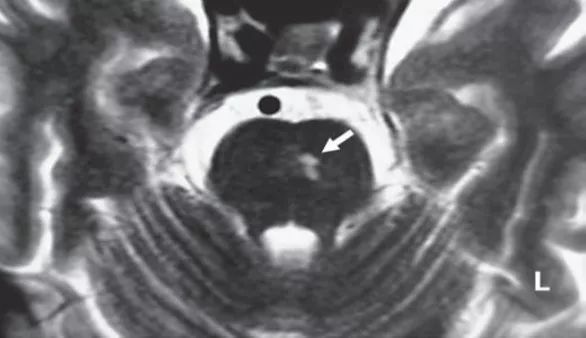

图2 病变累及VTT

脑桥病变在脑桥腹侧被盖(he ventral tegmentum)和或脑桥后基底部(the posterior basis pontis)。通常病变范围较大,且双侧受累。该区域的损伤恰好伤及兴奋性上向SVN-VTT前庭眼动传导束。